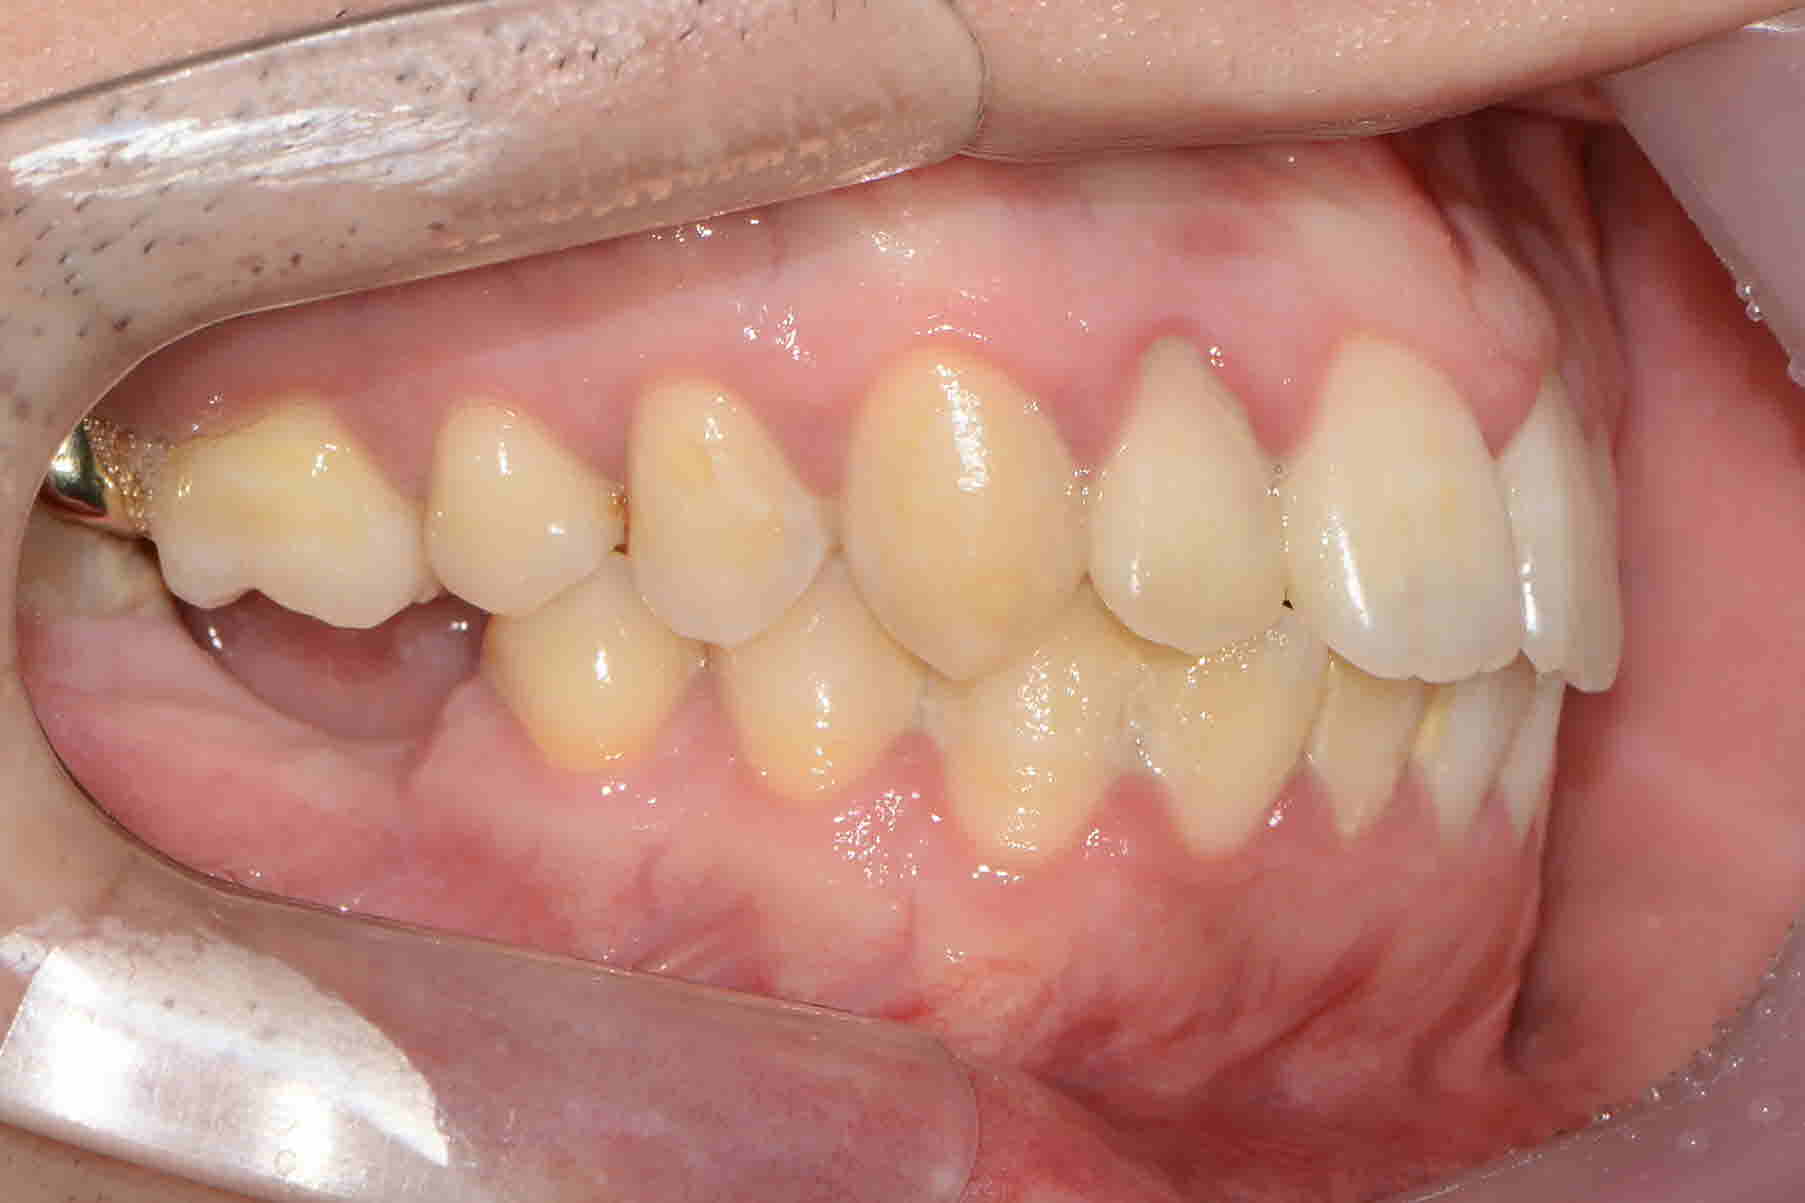

돌출입 고민으로 내원해주신 윤**님! 빠져있는 치아들로 임플란트도 계획중이셨는데요.위에 작은어금니 발치로 앞니들을 뒤로 이동시켜 돌출입을 개선하고 있는중입니다. 또 위치가 좋지않아 사용하지못하는 사랑니를 앞으로 당겨 임플란트 대신 쓰실 수 있게 교정진행중입니다.점점 더 멋진미소를 보여주시는 윤**님 교정마무리까지 최선을다하겠습니다. ^^

1 8년 7월 측면

19년 5월 측면